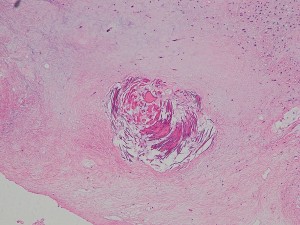

生後5ヶ月の女児に発生した右中頭蓋窩から海綿静脈洞から側頭下窩の成熟奇形腫です。腫瘍のう胞が大きく,右大脳半球の高度の圧排変形がみられます。

のう胞が巨大なので,まずのう胞腹腔シャントをして脳の変形を戻しました。その2ヶ月後に開頭手術で腫瘍を亜全摘出しています。

小児科から抗てんかん薬の投与を受けていますが学習障害などなくて正常です。また腫瘍再発もなく,看護学校へ通学しています。

左上の写真で見えるのは,腫瘍内部にあった小脳組織です。内胚葉,外胚葉性組織など多様に分化した組織が混入しています。

乳児の先天性奇形腫は手術摘出だけで治療できる良性の腫瘍です